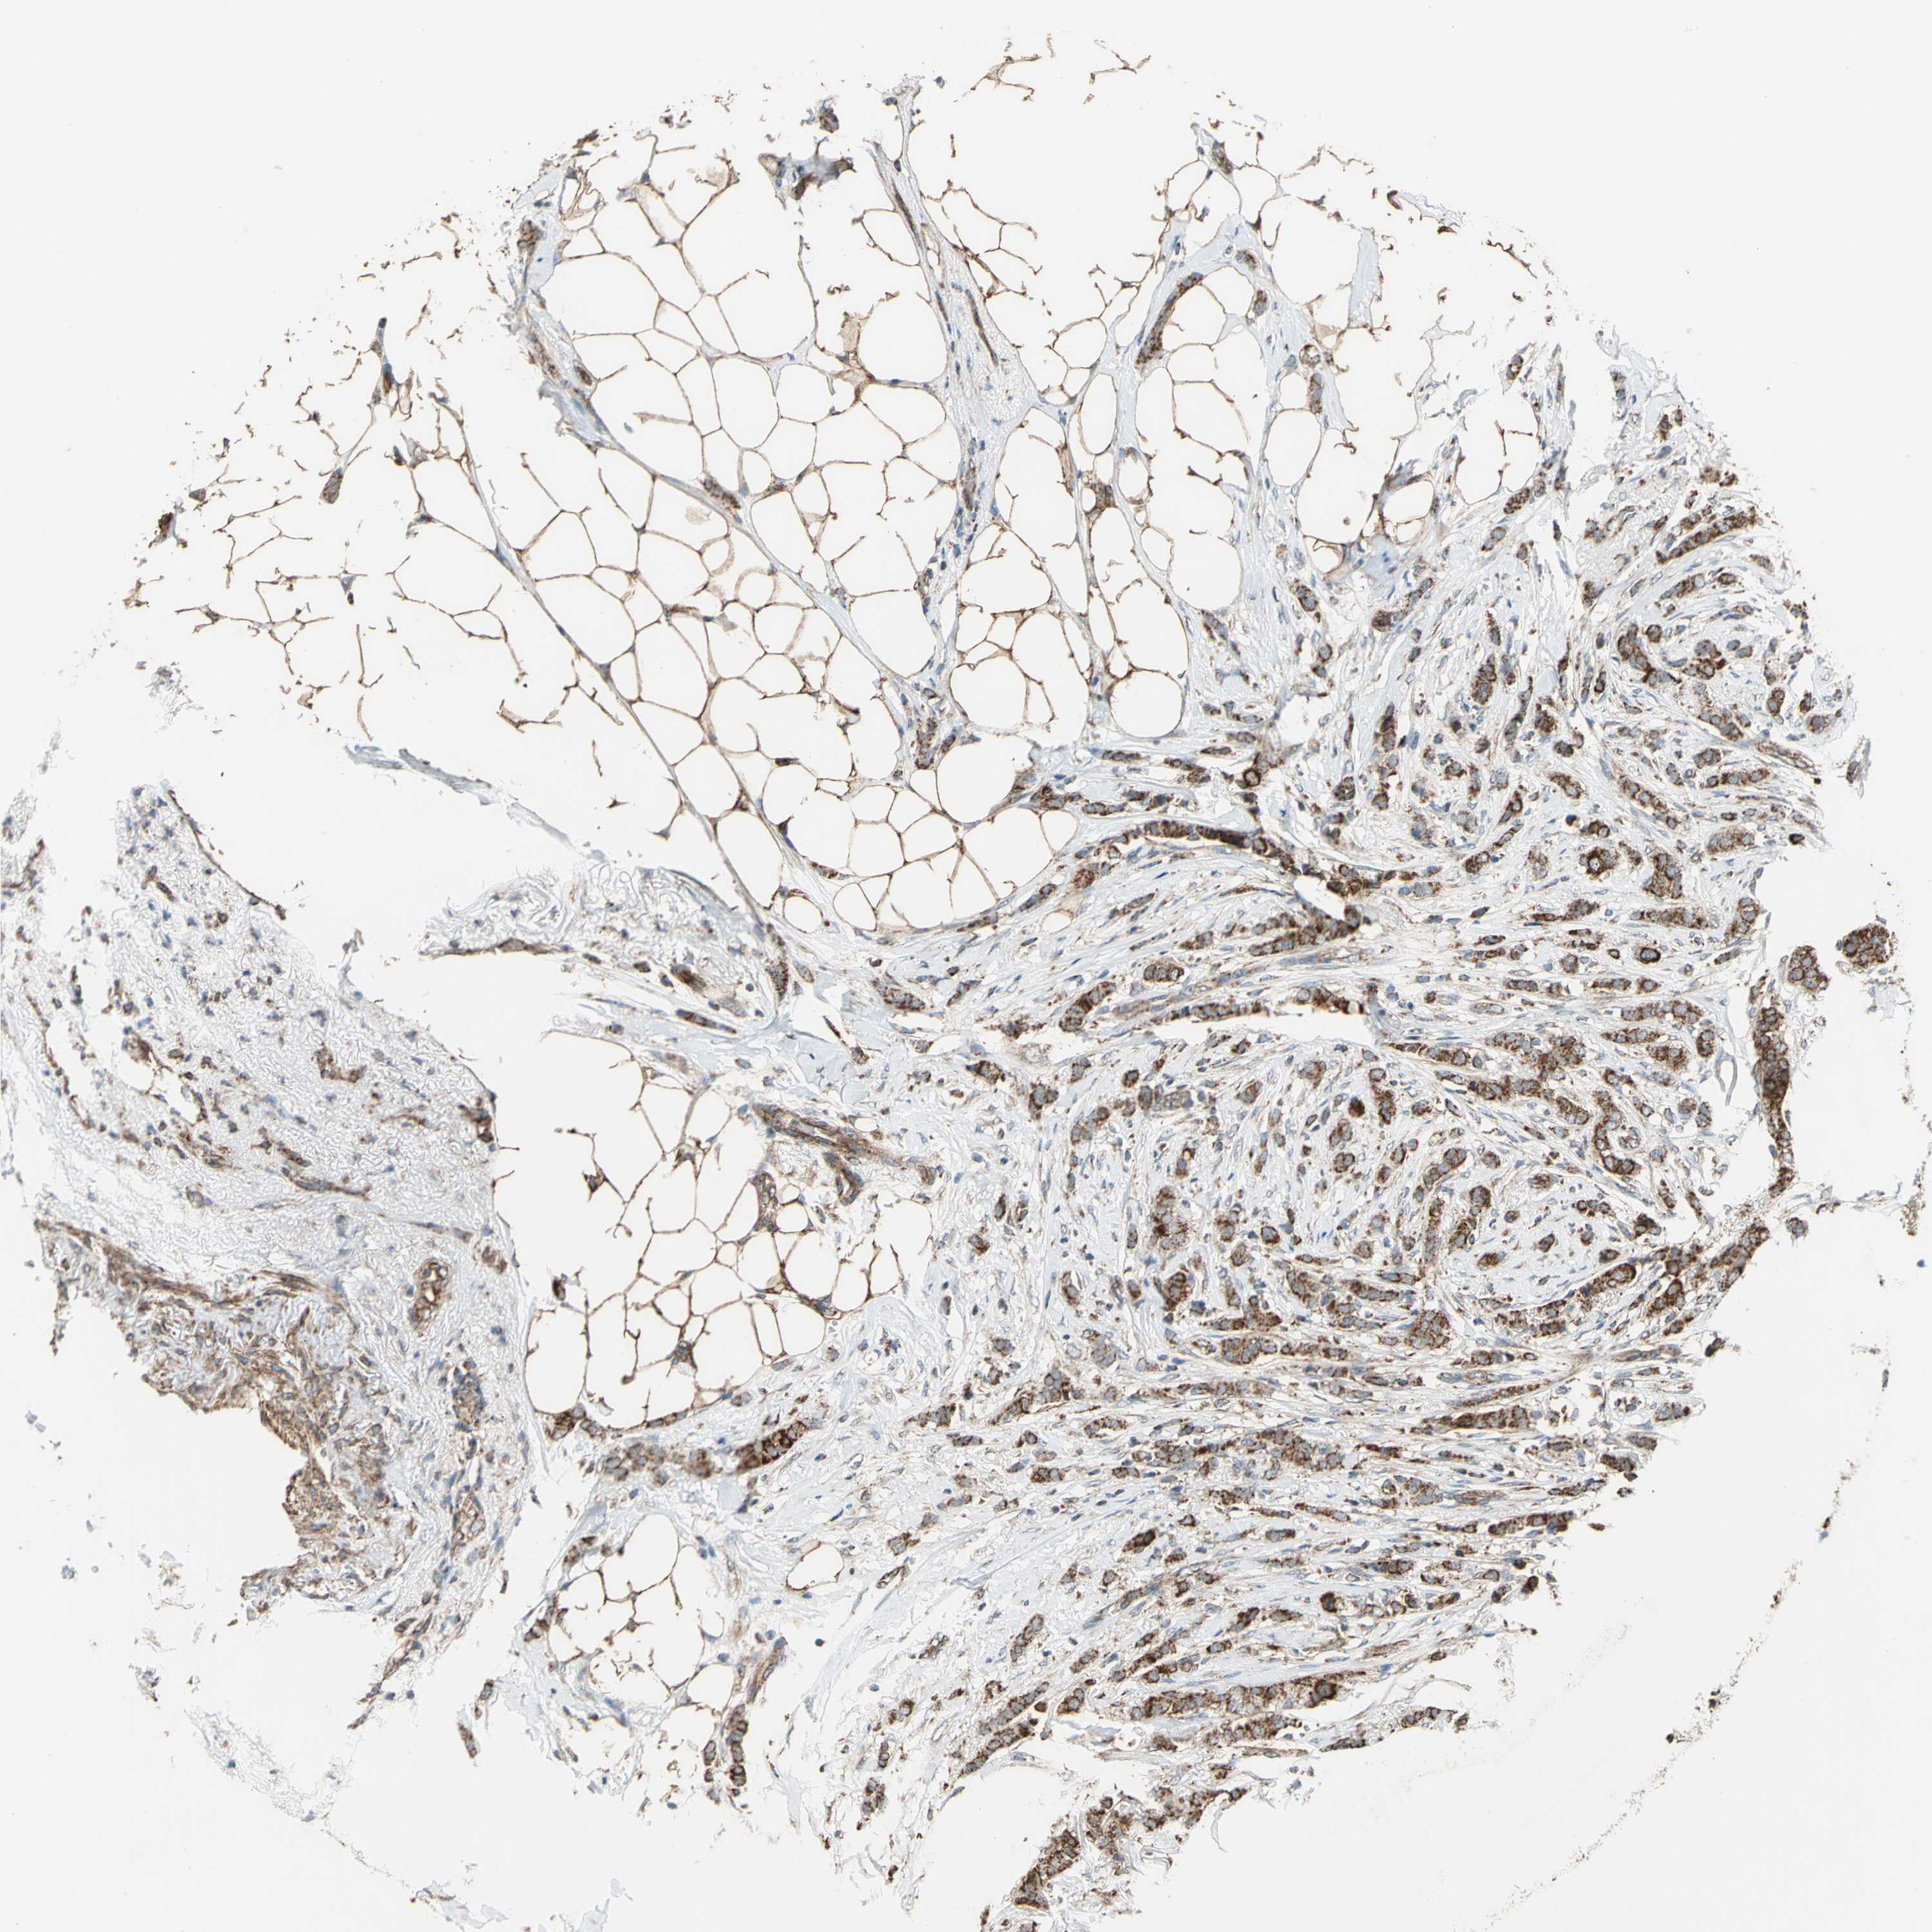

BRCA TCGA BRCA VALIDATION PROTEIN EXPRESSION